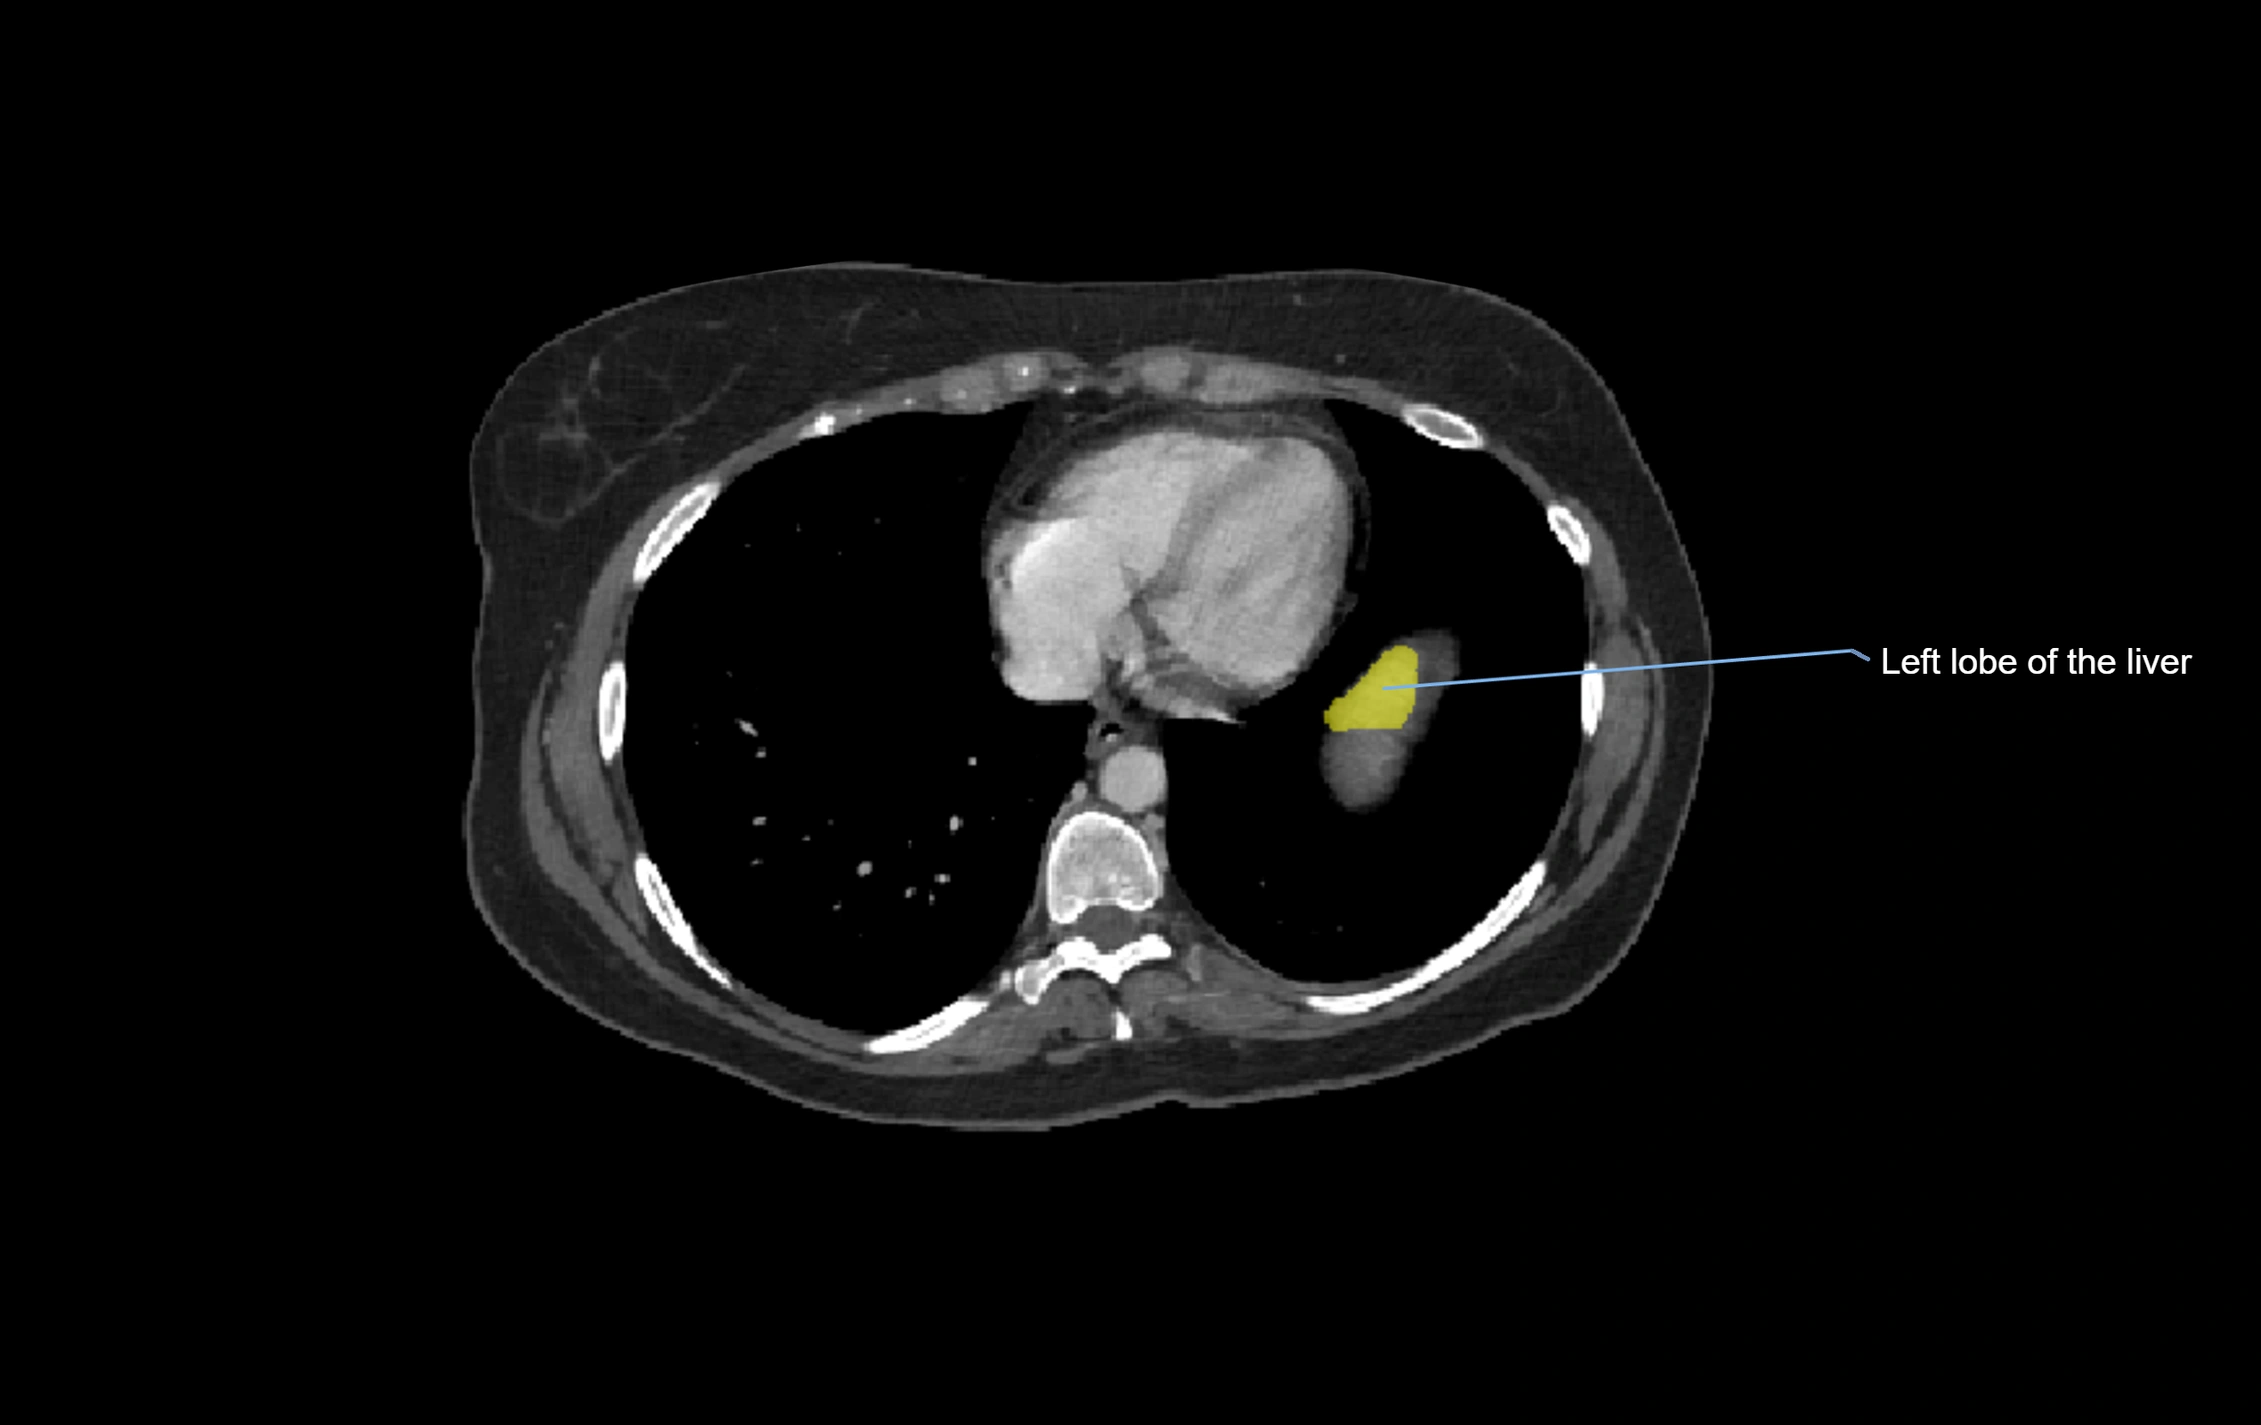

CT Image

image